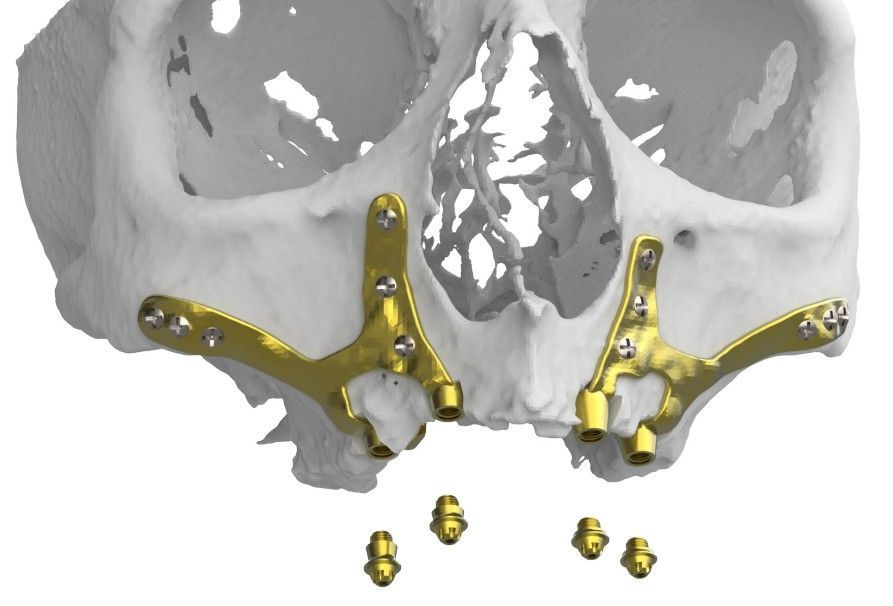

DISEÑO y Planificación de los Implantes Subperiósticos (ISP)

Definir la zona que se quiere tratar: Maxilar o Mandíbula

Definir el tipo de implante deseado: ISP parcial o ISP completo

En el caso de ISP completo definir si se quiere el diseño en una o dos partes

Detallar el número de conexiones totales del ISP

Detallar si se requiere de guía de corte en poliamida o titanio

Detallar si requiere un modelo 3D en poliamida del maxilar o mandíbula

Detallar si requiere de un modelo 3D en poliamida del ISP

Detallar si requiere de una barra de posicionamiento para la carga inmediata de la prótesis